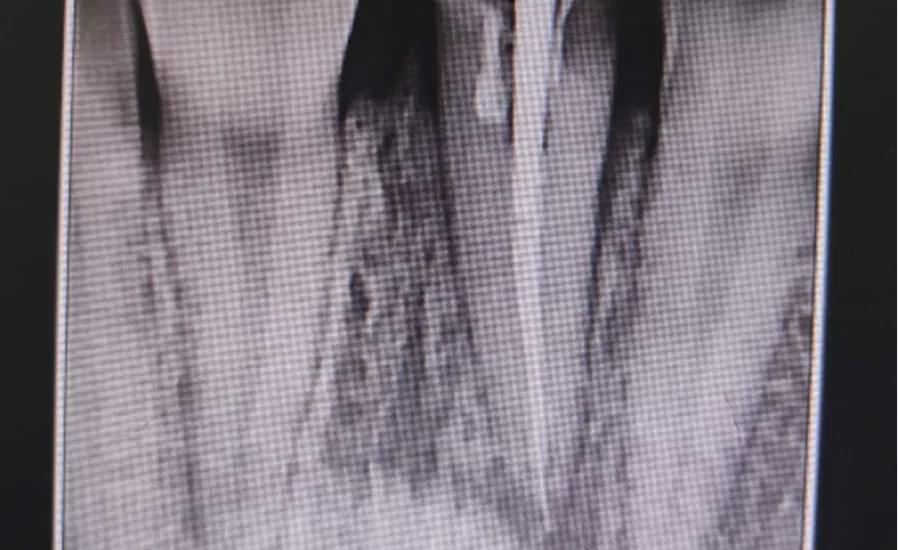

“經(jīng)檢查,患者患牙冠冠根聯(lián)合折,折斷面位于齦下2mm,患牙唇側(cè)傾斜,缺牙間隙較大,拍片檢查患牙牙根長(zhǎng)度尚可,殘留牙根未見(jiàn)明顯折斷,還有機(jī)會(huì)可以讓它恢復(fù)如初。”駐馬店市中心醫(yī)院口腔科值班醫(yī)生杜驛明為患者完善檢查后的一番話,讓張女士心里有了重塑美麗的希望。

經(jīng)過(guò)會(huì)診,一致決定由杜驛明醫(yī)生為患者完善根管治療,王利民醫(yī)生植入纖維樁,利用光固化樹(shù)脂制作臨時(shí)牙,劉小東醫(yī)生行合向+腭向牽引牙根,同時(shí)關(guān)閉前牙間隙。

經(jīng)過(guò)3個(gè)月的正畸治療,張女士的門牙斷面位于齦上,間隙消失,牙列整齊,完美的恢復(fù)了患者牙齒的美觀,患者非常滿意。